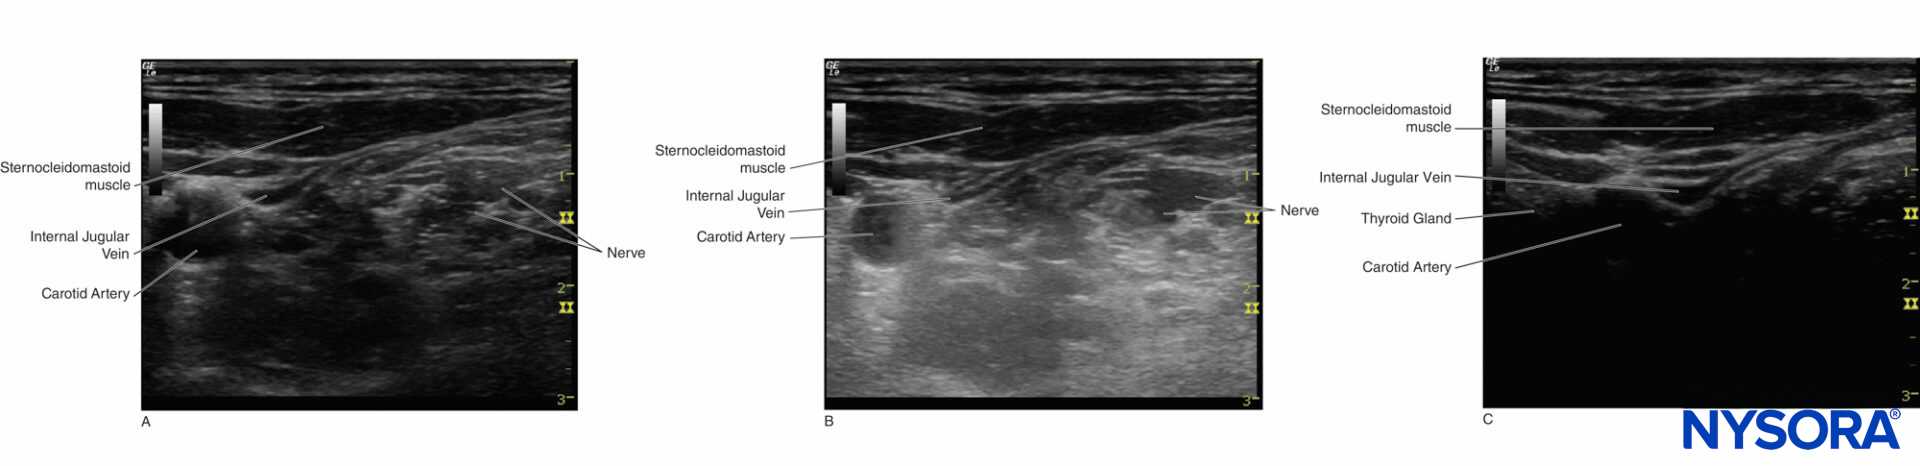

Figure 13. Color Doppler mode is used to detect the direction of the blood vessel.

In ultrasound-guided peripheral nerve blocks, color Doppler mode is used to detect the presence and nature of the blood vessels (artery vs. vein) in the area of interest. When the direction of the ultrasound beam changes, the color of the arterial flow switches from blue to red, or vice versa, depending on the convention used (Figures 13, 14A, 14B, and 14C). Power Doppler is up to five times more sensitive in detecting blood flow than color Doppler, and it is less dependent on the scanning angle. Thus, power Doppler can be used to identify the smaller blood vessels more reliably. The drawback is that power Doppler does not provide any information on the direction and speed of blood flow (Figure 15).

Figure 14. A: Carotid artery displays a red color when the blood flows toward the transducer. B: Carotid artery displays ambiguous color at a 90° Doppler angle; the equal waveform can be seen on both sides of the baseline. C: Carotid artery displays blue color when the blood flows away from the transducer.